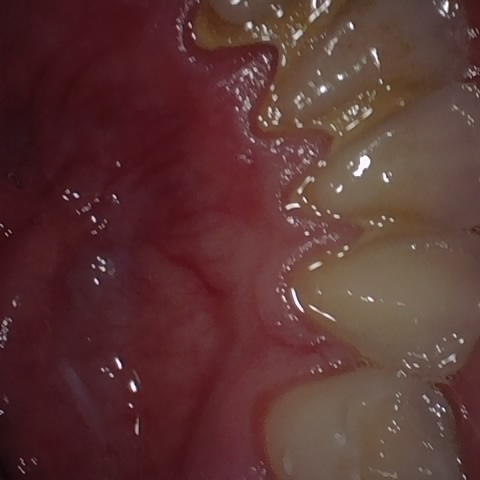

Annotated as "Good"